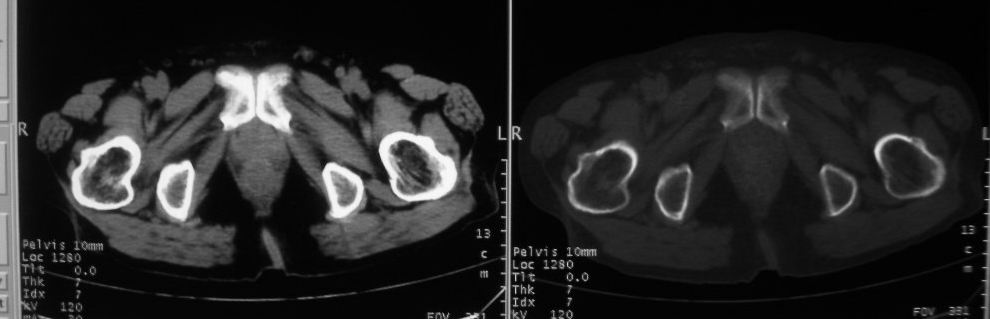

以下是引用zjzjr在2008-10-3 12:59:00的发言:[br]前列腺癌伴左髂骨\\腰椎转移可能性大.

以下是引用卜一在2008-10-3 13:40:00的发言:[br]前列腺癌!左髂骨\\腰椎转移?建议行全身骨扫描!

以下是引用深泽交通医院在2008-10-3 15:33:00的发言:[br]前列腺实性增大伴分叶状,与包膜间隙境界不清;椎体松质区间结节样密度影,考虑:前列腺癌,并椎体成骨性转移